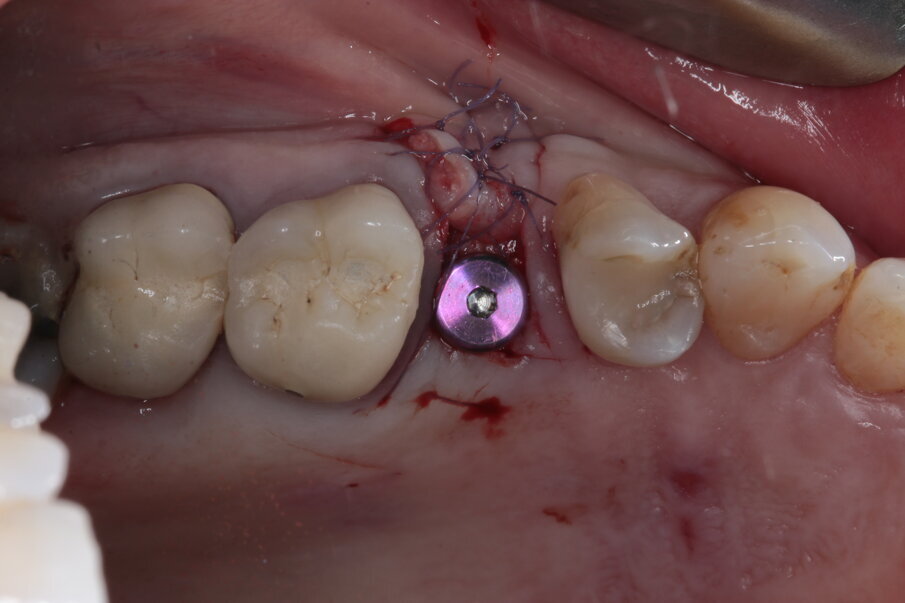

Viene disegnato un roll flap, posizionato l’impianto tramite una mascherina di guida per la fresa pilota ottenuta tramite stampa 3D, inserita una vite di guarigione transmucosa e suturato il lembo. Dalle immagini intraoperatorie si può notare come la scelta di materiale a rapido riassorbimento abbia permesso l’ottenimento di un osso vitale, sanguinante e con la quasi totale assenza di particelle di biomateriale ancora presenti. L’imprecisione nella sutura della porzione distale del lembo genererà uno spessore maggiorato del connettivo in quella zona, che avrà come effetto un piccolo inestetismo che tuttavia la paziente non nota e che non intende correggere (Figg. 14-17). Al termine dei 4 mesi necessari al completamento del processo di osteointegrazione, viene inserito un provvisorio avvitato con il quale inizia il condizionamento dei tessuti perimplantari.